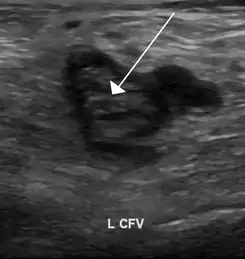

![]() Una imagen de ultrasonido que muestra un coágulo de sangre en la vena femoral común izquierda. | ||

La mayoría de las personas que tienen una trombofilia no presentan síntomas. No obstante, algunas desarrollan un coágulo de sangre, o trombosis. Con frecuencia, los coágulos sanguíneos se forman en las venas de la parte inferior de la pierna y producen hinchazón, enrojecimiento y malestar. Este trastorno, llamado trombosis venosa profunda, suele diagnosticarse mediante métodos de diagnóstico por imágenes que emplean ultrasonidos. Los coágulos suelen tratarse con medicamentos anticoagulantes.